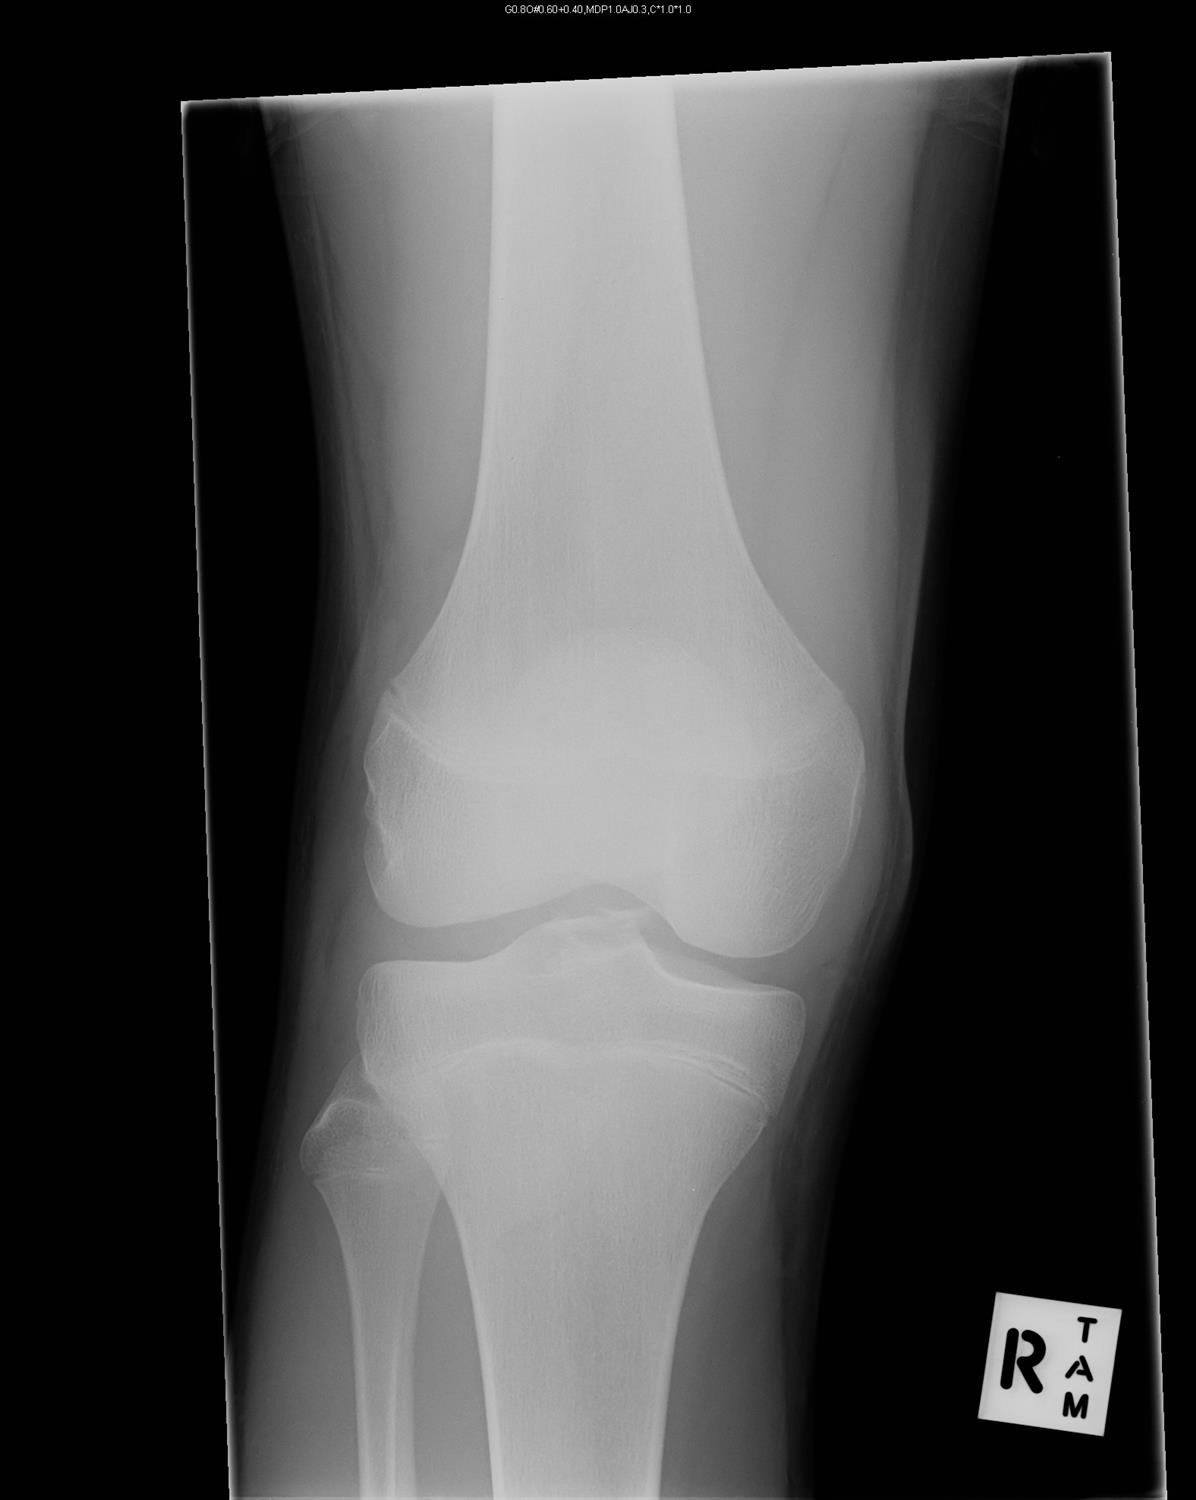

Knee Imaging Knee & Sports Orthobullets Sports Orthobullets Medial meniscus has less mobility with more rigid peripheral fixation than the lateral meniscus. Common activities are soccer, basketball, skiing, and football. Posterolateral corner (plc) injuries are traumatic knee injuries that are associated with lateral knee instability and usually present with a concomitant cruciate. Flex the knee and place a hand on medial side of knee, externally rotate the leg. Sports Orthobullets.